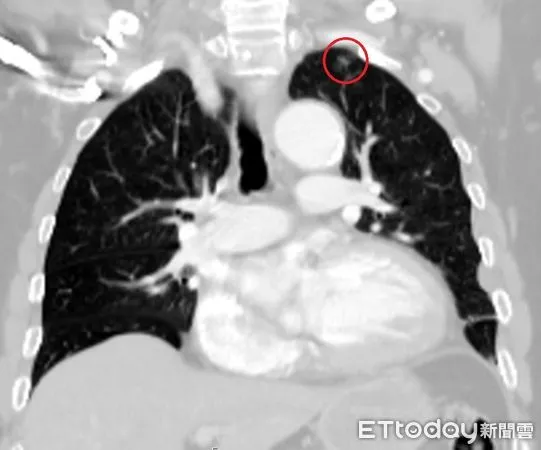

▲光田醫院搶救林男時,電腦斷層意外發現林男肺部邊緣出現一處僅0.9公分的肺結節陰影,事後證實是早期肺腺癌。(圖/光田醫院提供)

台中一名林姓男子因車禍造成肋骨多處骨折、胸腔積水,被送到醫院急救,結果就在醫師與影像醫學科團隊仔細檢視電腦斷層時,意外發現林男肺部有一個小於1公分的腫瘤,醫師進行手術搶命同時也切除腫瘤,最後病理報告也證實為肺腺癌,讓這個原本可能潛伏多年、毫無症狀的病灶,因車禍而被提早發現,讓男子免於癌王威脅。

陳紀寰說明,肺腺癌是目前最常見的肺癌類型,偏好生長在肺部邊緣,由於位置較靠外側,初期不易侵犯位置較內側的氣管、神經或血管,因此多數患者在早期幾乎沒有明顯症狀,可能在體內「無聲無息」潛伏多年,等到被發現時往往已是晚期。